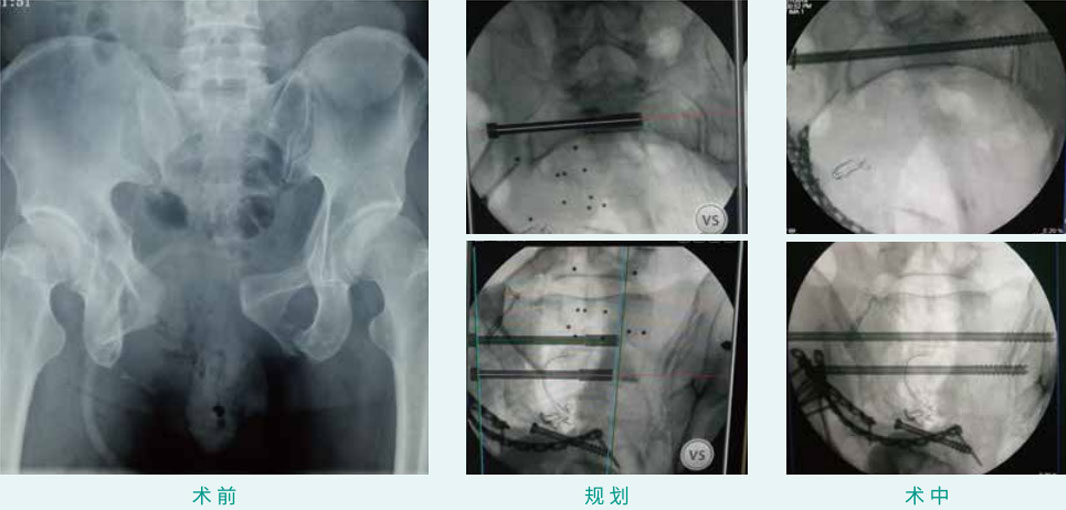

天玑? 辅助骶髂螺钉(骶1、骶2)经皮空心螺钉内牢靠术

基本情形:患者男,,,,,,,27岁,,,,,,,骨盆骨折

机械人累积用时:15分钟

植入物:2枚空心螺钉

病例泉源:中国人民解放军总医院(301医院) 陈华